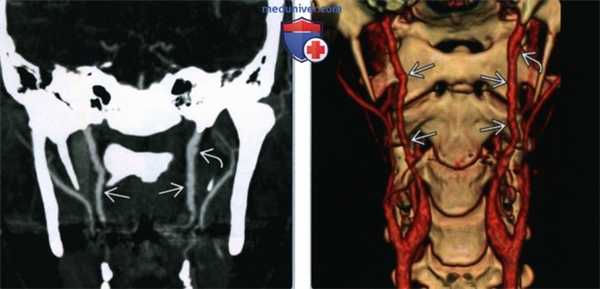

(Слева) Схема бифуркации общей сонной артерии, показаны основные варианты фиброзно-мышечной дисплазии. Тип 1 -чередующиеся участки сужения и расширения сосуда S3; тип 2 - протяженный участок стеноза; тип 3-участки неровности с формированием дивертикула.

(Справа) КТ-ангиография, реконструкция в сагиттальной проекции. Деформация внутренней сонной артерии по типу «четок». При более детальном рассмотрении обеих артерий также удалось обнаружить участки выпячивания сосудов, которые характерны для дисплазии 3 типа.

(Слева) КТ-ангиография, коронарная проекция. Женщина 44 лет с фиброзно-мышечной дисплазией: определяется нечеткость контуров обеих внутренних сонных артерий, которая весьма характерна для фиброзно-мышечной дисплазии. В левой сонной артерии имеется участок расслоения с формированием псевдоаневризмы.

(Справа) Объемное изображение, КТ-ангиография в коронарной проекции, эта же пациентка. Здесь аневризма левой внутренней сонной артерии видна более четко. Вновь можно увидеть неровные контуры обоих сосудов, которые характерны для фиброзно-мышечной дисплазии.